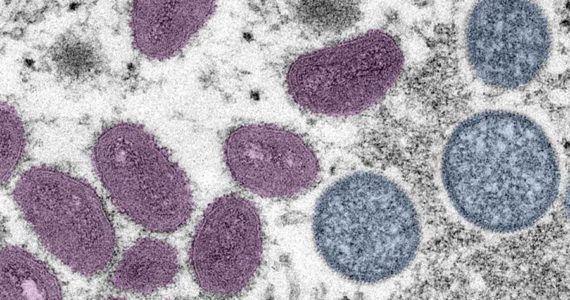

As of Aug. 3, at least 166 people in Washington had tested positive for the monkeypox virus.

State has been allotted 398 courses of the 2-dose JYNNEOS monkeypox vaccine.

Washingtonians can now call 1-833-829-HELP for any questions relating to the monkeypox virus.